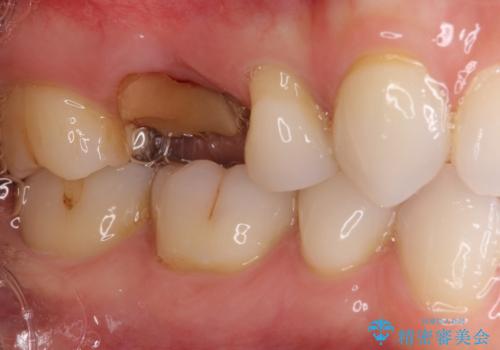

- 近医で奥歯の抜歯が必要であると指摘され、インプラント治療を希望して来院された患者様です。

診察の結果、大きな虫歯となっている歯は抜歯が望ましく、抜歯後にストローマンSLActiveを埋入することとしました。

さらに後方の歯は虫歯治療が途中であったため、ゴールドインレーにて修復治療行うこととしました。